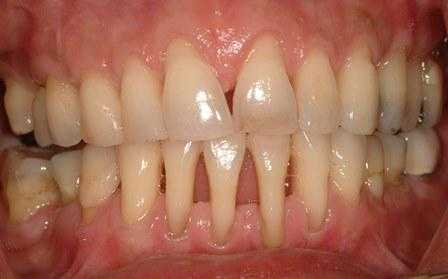

Эндодонто-пародонтальные поражения (ЭПП) - сложная проблема современной стоматологии, так как их диагностика и лечение требуют от врача знаний в области пародонтологии и эндодонтии (рис. 1, 2).

Рис. 1. ЭПП в области зубов 24 и 25.